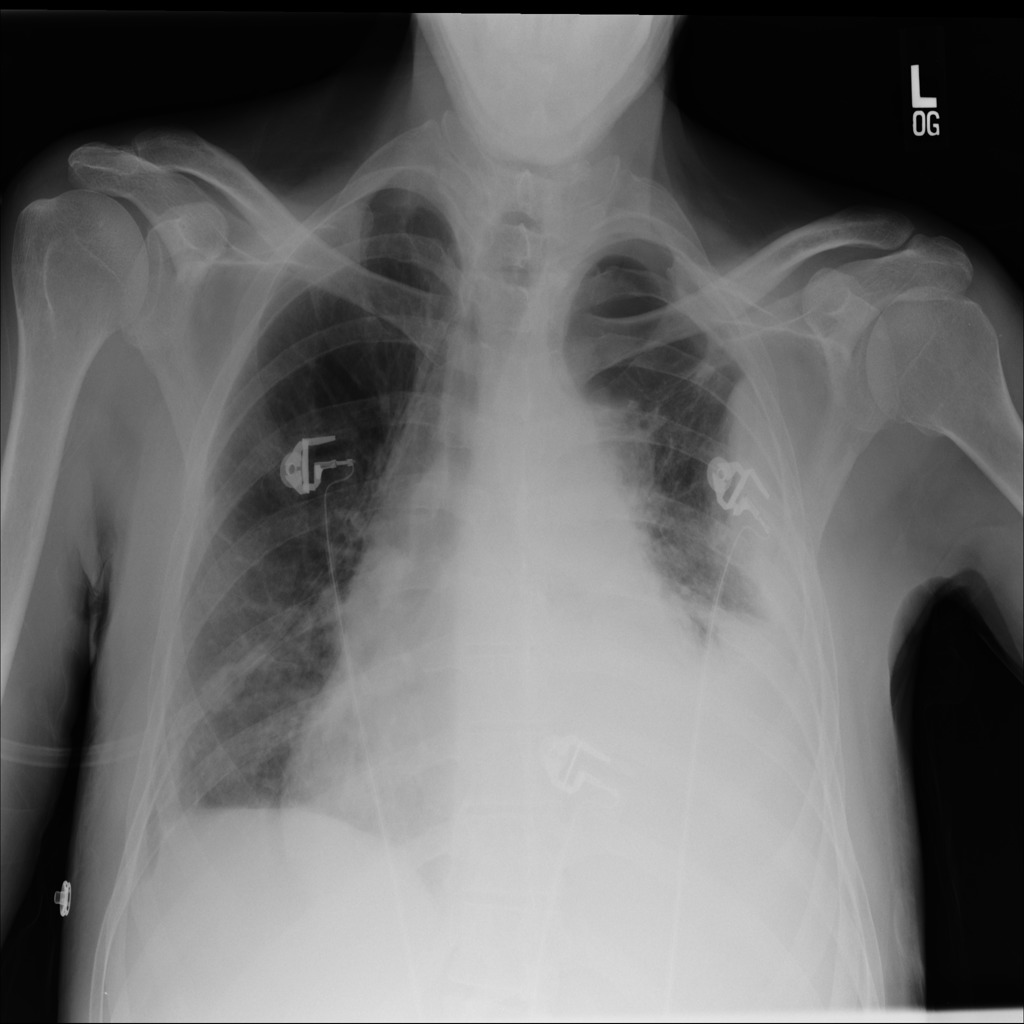

Refer to caption

(a) Image

(b) Step1.CAM

Figure 1: Pneumothorax localization maps for (a) a random image from the test set at each consecutive step of our method: (b) map after CAM extraction, (c) improved map by IRNet trained on the outcomed of step 1, (d) prediction of U-Net trained on step 2 results, all compared to (e) ground truth mask.